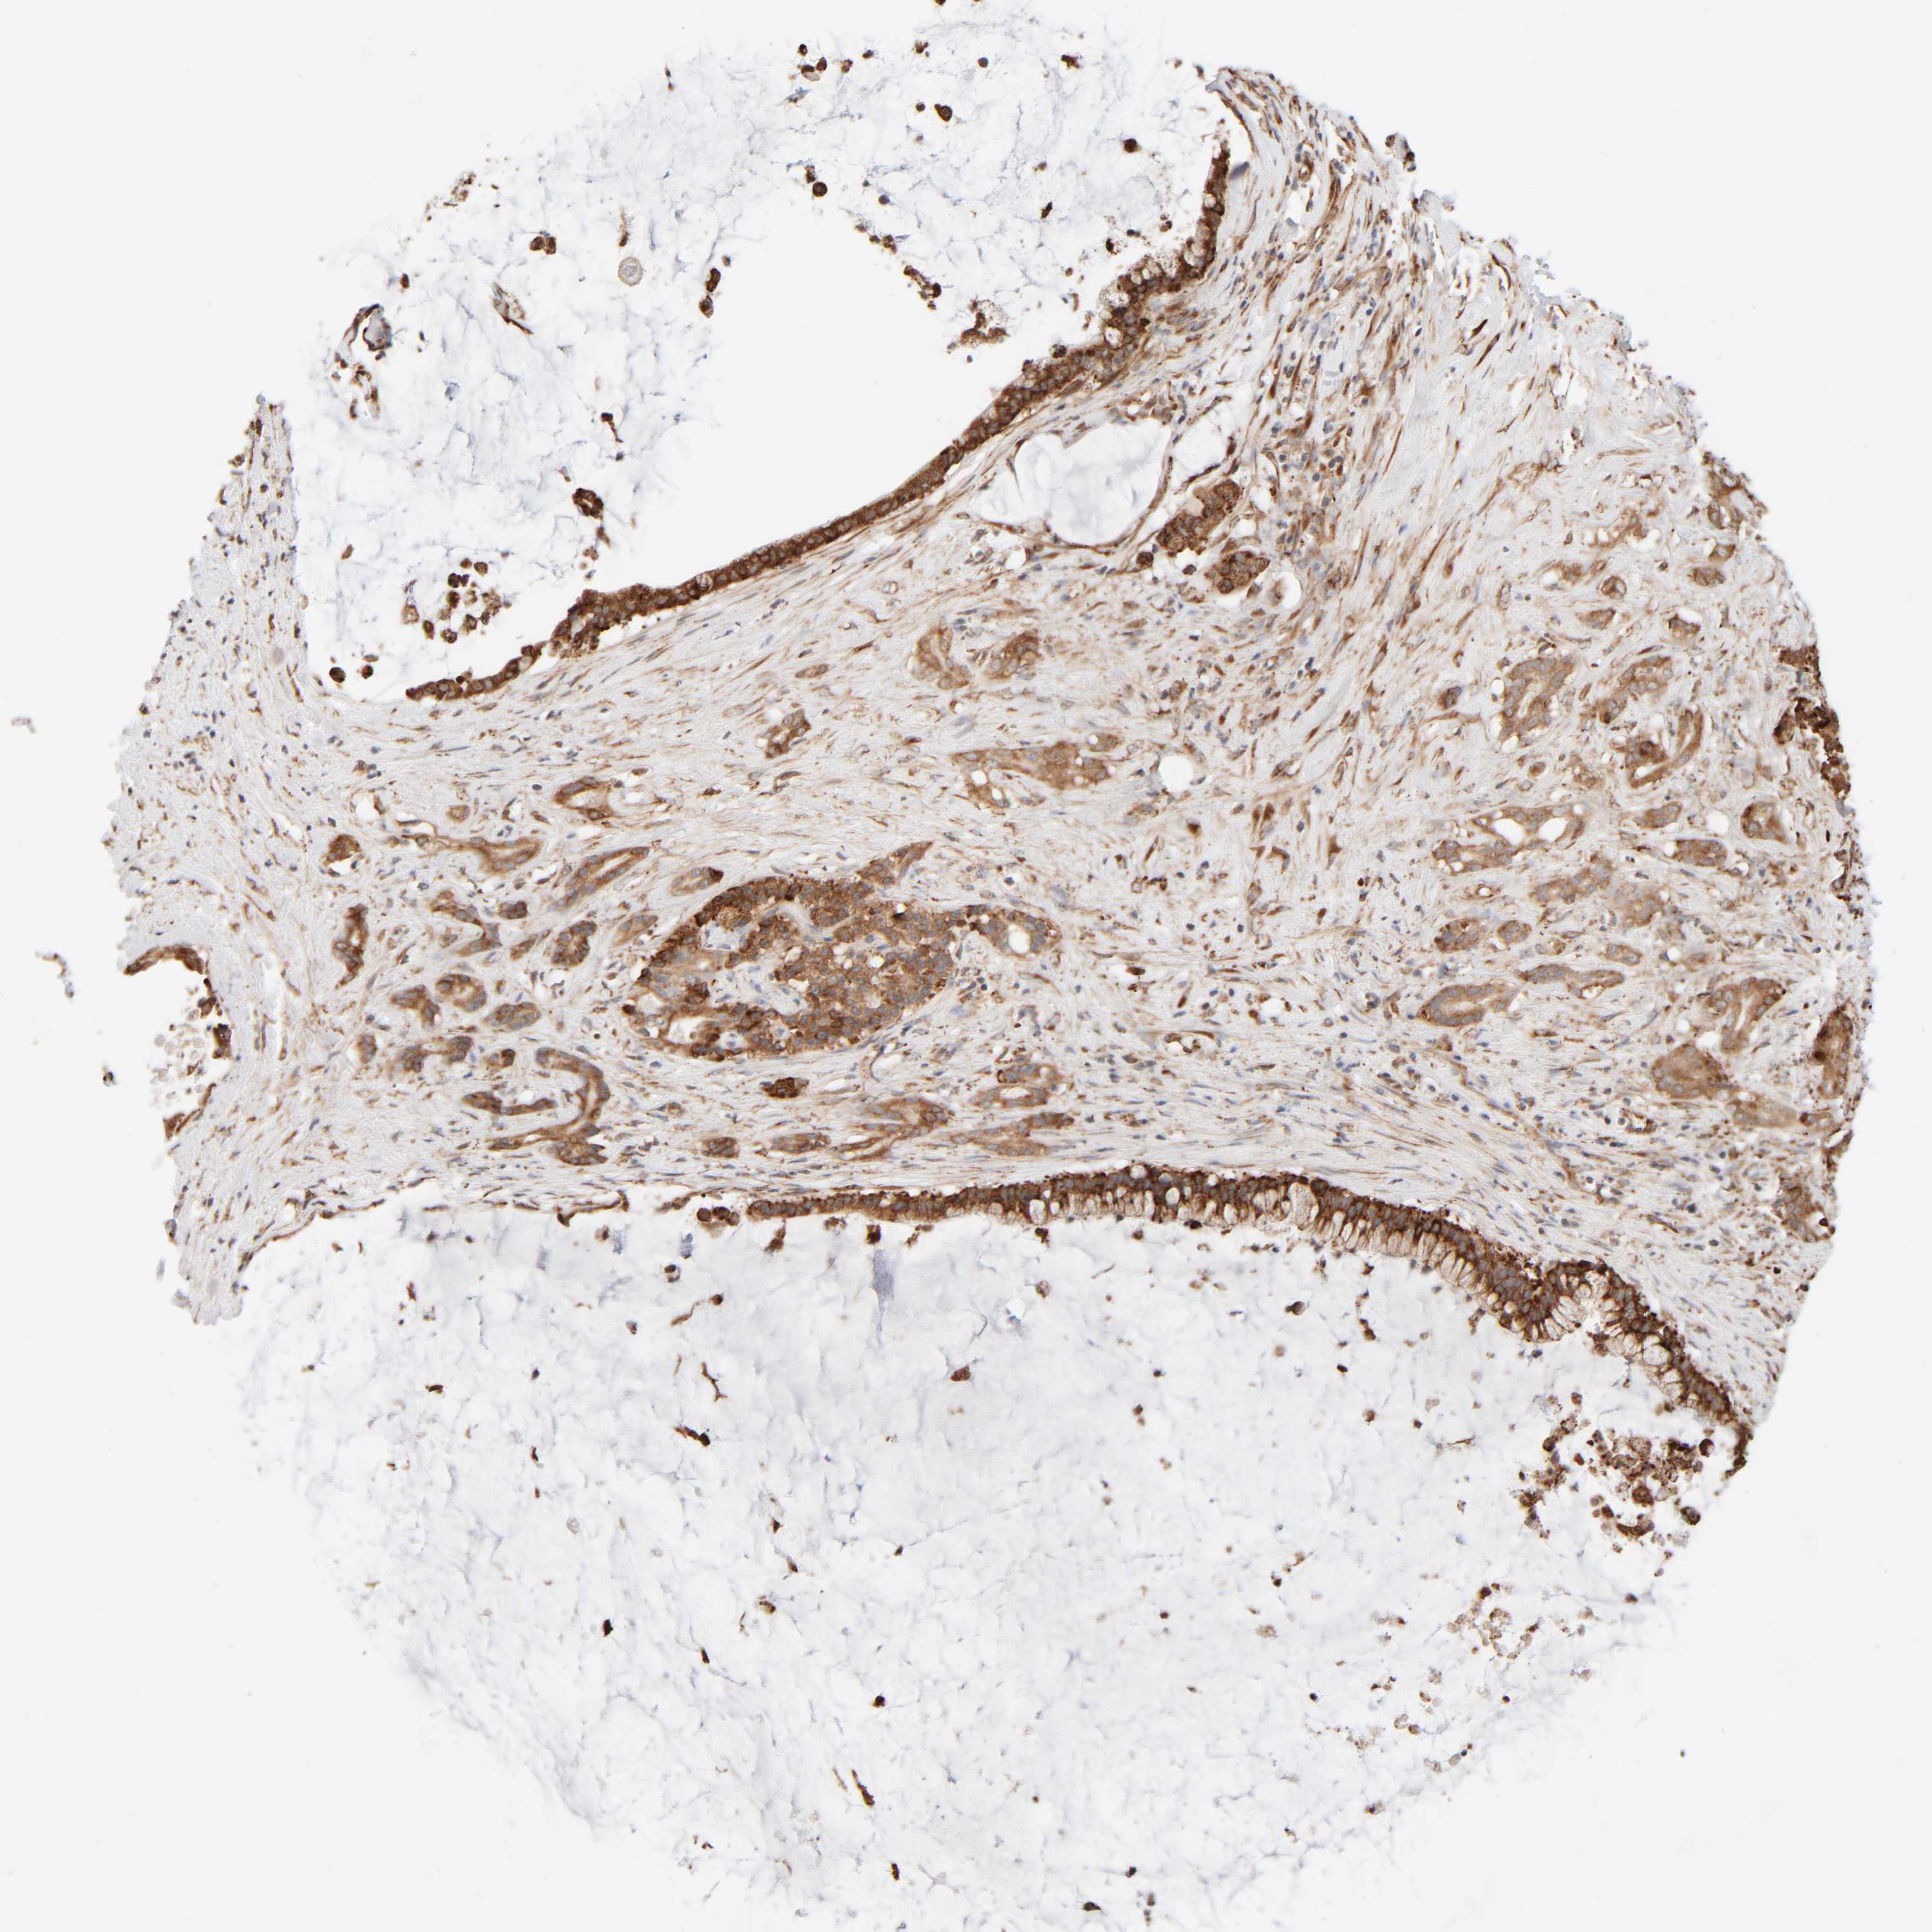

PANCREATIC CANCER - Protein expressioni

A mouse-over function shows sample information and annotation data. Click on an image to view it in a full screen mode. Samples can be filtered based on level of antibody staining by selecting one or several of the following categories: high, medium, low and not detected. The assay and annotation is described here.

Note that samples used for immunohistochemistry by the Human Protein Atlas do not correspond to samples in the TCGA dataset.

Antibody stainingi

Antibody staining in the annotated cell types in the current human tissue is reported as not detected, low, medium, or high, based on conventional immunohistochemistry profiling in selected tissues. This score is based on the combination of the staining intensity and fraction of stained cells.

Each image is clickable and will lead to virtual microscopy that enables deeper exploration of all samples and also displays staining intensity scores, fraction scores and subcellular localization as well as patient and tissue information for each sample.

Antibody HPA021658

Staining

High

Medium

Low

Not detected

Intensity

Strong

Moderate

Weak

Negative

Quantity

>75%

75%-25%

<25%

None

Location

Nuclear

Cytoplasmic/membranous

Cytoplasmic/membranous,nuclear

Adenocarcinoma, NOS